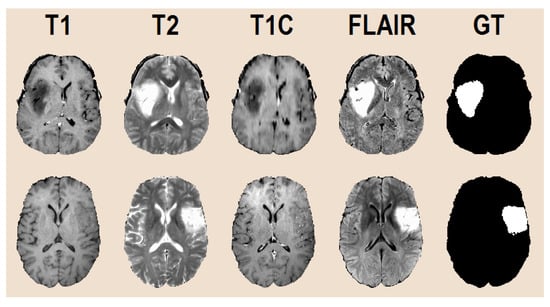

The records in each set have the same format. Records are multi-spectral, which means that every pixel in the volumes has four different observed intensity values (named T1, T2, T1C, and FLAIR after the weighting scheme used by the MRI device) recorded independently of each other and registered together afterwards with an automatic algorithm. Each volume contains 155 square shaped slices of pixels. Pixels are isovolumetric as each of them represents brain tissues from a 1 mm3 sized cubic region. Pixels were annotated by human experts using a semi-automatic algorithm, so they have a label that can be used as the ground truth for supervised learning. Figure 2 shows two arbitrary slices, with all four observed data channels, and the ground truth for the whole tumor, without distinguishing tumor parts. Since the adult human brain has a volume of approximately 1500 cm3, records contain around 1.5 million pixels. Each record contains gliomas of a total size between 7 and 360 cm3. The skull was removed from all volumes so that the researchers can concentrate on classifying brain tissues only, but some of the records intentionally had missing or altered intensity values, in the amount of up to one third of the pixels, in one of the four data channels. An overview of these cases is also reported in Table 1.

Figure 2.

Input data after pre-processing (T1, T1C, T2, FLAIR) and the human expert made ground truth (GT) for the whole tumor segmentation problem.